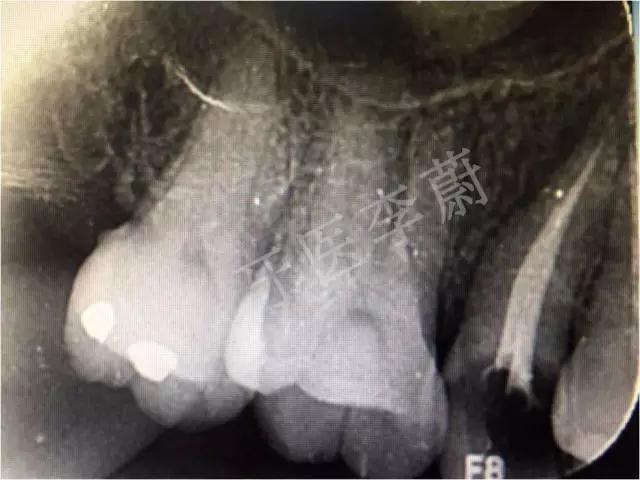

X片示:15残冠影,根尖有骨密度降低影。

局部X牙片

15牙根管充填术后X牙片